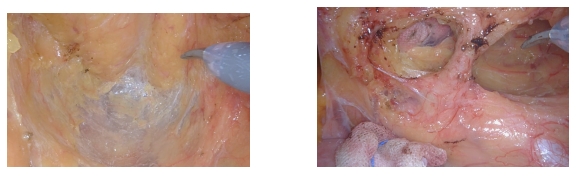

近日,江西省人民医院(南昌医学院第一附属医院)胃肠外科接诊了一名直肠癌患者,经检查,患者的肿瘤距离肛门仅有2厘米。由于患者保肛愿望强烈,科主任廖新文带领团队与普外科、肿瘤科、影像科等学科开展MDT,最终决定:利用达芬奇机器人,为患者实施精准的超低位保肛手术,避免患者终身携带“粪袋”,保障其今后的生活质量。

②机器人机械臂的540度旋转功能,使其在骨盆等狭窄区域的操作更加灵活,特别适合应对复杂的解剖结构。

③达芬奇机器人操作精准,具备防震和防雾功能,手术出血量显著减少,同时还能实现超低位保肛手术,特别有利于复杂低位直肠癌患者的治疗。